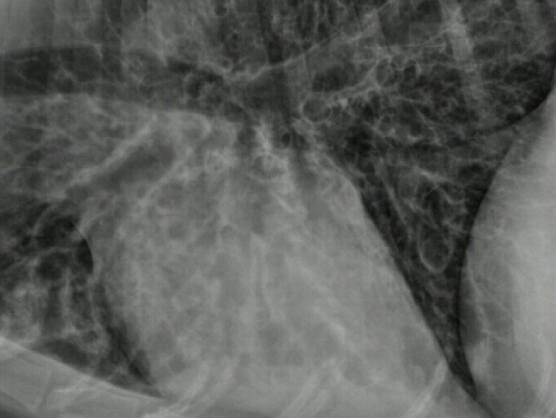

What lung pattern?

Bronchial pattern (see doughnuts)

What lung pattern? What are the arrows pointing to?

Bronchial pattern

tram tracks

Lung pattern?

diffuse severe bronchial pattern